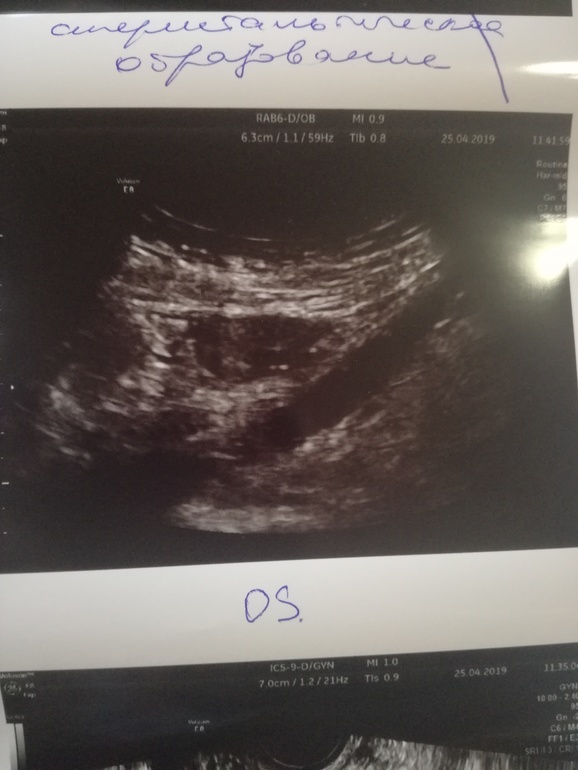

УЗИ, всё плохо?

Девочки, пожалуйста , скажите что здесь насмотрели у меня . Глаза на мокром месте, одна труба левая , правая удалена